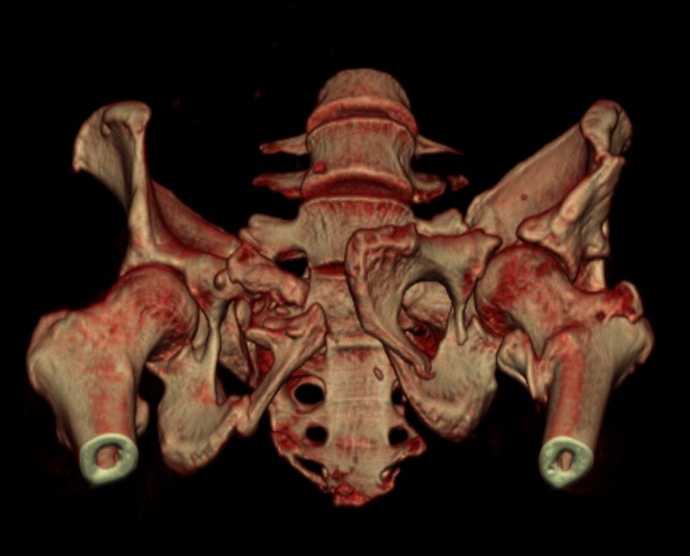

Больная 43 года (промышленный альпинист), 28.07.08 в результате падения с 5 этажа получила политравму:

Перелом свода и основания черепа. Вертикально-нестабильное повреждение таза, осложнённое разрывом мочевого пузыря. Чрезвертельный перелом левого бедра. Перелом правой таранной кости, переломовывих правой кубовидной кости. Тупая травма живота, разрыв печени, ушиб почек. Забрюшинная гематома. В день травмы - лапаротомия, ушивание ран печени. Разрыв мочевого пузыря не диагностирован. Течение болезни осложнилось развитием мочевого затёка и обширной пред- и забрюшинной флегмоны, сформировался свищ мочевого пузыря. 19.8.2008 вскрытие, дренировние флегмоны, ревизия мочевого пузыря, обтурация мочевого свища (свищ закрылся в октябре), 1.10.2008 некрэктомия, пластика по Шеде-Лидскому правой кубовидной кости. По результатам КТ диагностирован рак правой почки (диагностическая находка), 8.10.2008 нефрэктомия справа.

Переломы велись консервативно.

Имеется вертикальное смещение левой половины таза с выраженным отведением крыла (клинически подвижности нет), несросшийся низкий двухколонный перелом левой вертлужной впадины с потерей конгруэнтности, укорочение около5 см, застарелый разрыв лонного сочленения, неправильно сросшиеся переломы обеих ветвей правой лонной кости с укорочением, патологическая подвижность лоно-седалищного фрагмента слева. Правая нижняя конечность неопорна, несмотря на то, что лежа прямую ногу поднимает, ходит на левой ноге (ортопедическая обувь) с костылями, справа тазобедренный ортез. Седалищные нервы работают.Урологи отпустили больную на 6 мес.